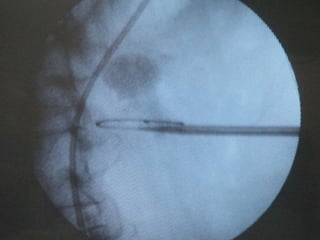

O documento discute o tratamento de urolitíase, especificamente a remoção de cálculos renais através de nefrolitotripsia. A cirurgia aberta é agora muito restrita devido aos avanços da ESWL e procedimentos endourológicos menos invasivos como ureteroscopia e cirurgia percutânea. A cirurgia laparoscópica está substituindo a cirurgia aberta como técnica menos invasiva que combina a tecnologia endourológica com a laparoscópica preservando